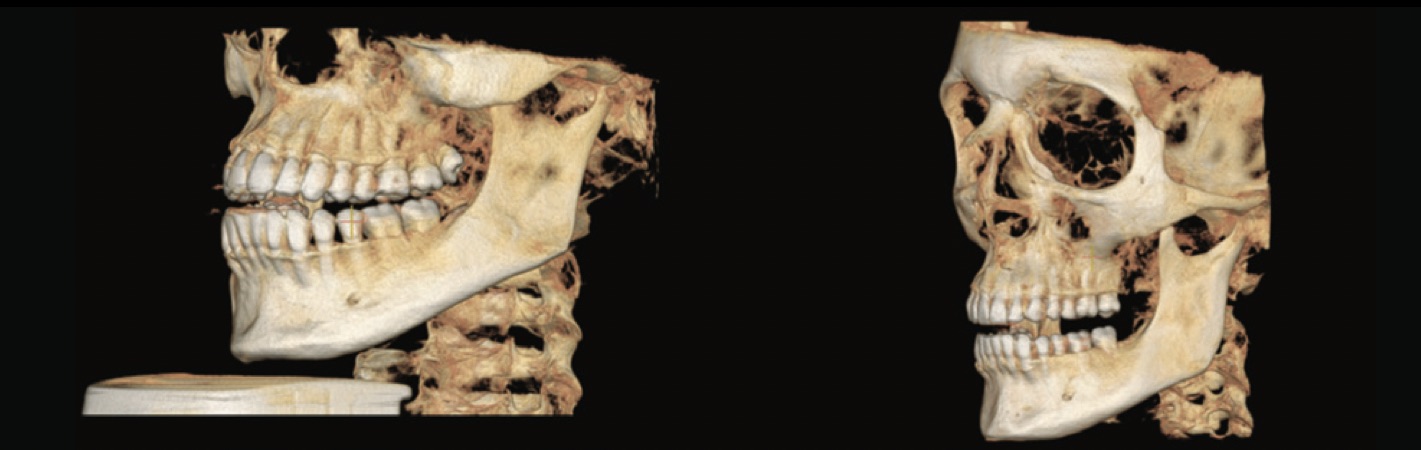

Image comparison: CBCT FOV 16 x 10 versus FOV 15 x 15.

Unlike 2D digital images, 3D images are constructed of voxels rather than pixels. The voxel is the smallest element of the 3D radiographic image volume and its size is given by its height, width and depth. In CT the voxels are anisotropic, which means they are not identical in all planes as their height depends on the thickness of the CT beam, i.e. the plane thickness, which means that in certain planes such as the sagittal plane the precision is limited as it depends on the distance of the slices (gap). In contrast, in CBCT the voxels are isotropic, identical in height, width and depth and this allows geometrically more precise images in any plane.

3D cephalometric analysis: forget about the limitations of 2D radiology such as errors in patient positioning, magnification of bilateral structures and the superimposition of other craniofacial structures, and obtain a 3D image of vital structures with better localisation of anatomical marks in cephalometric analysis.